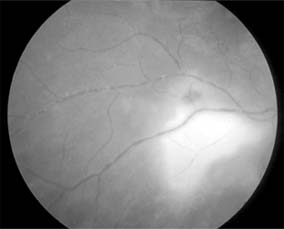

Figure 15-29: Toxoplasmosis. Active area of chorioretinitis adjacent to scar with reaction in adjacent retinal arteriole.

A focal choroiditis is seen, usually in the posterior pole, and an active lesion is often related to an old healed lesion. Episodes of posterior uveitis and chorioretinitis usually represent reactivation of a congenital infection. Rarely, panuveitis may occur, or optic neuritis progressing to optic atrophy. Isolated anterior uveitis does not occur. Peripheral vision is usually preserved, but because of macular involvement in at least 50% of cases, central vision is reduced.